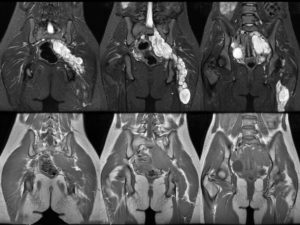

При должной квалификации врача, ни что не останется не замеченным. Для пациента же результат исследования отчасти напоминает рентгеновский снимок и выглядит следующим образом.

МРТ органов малого таза проводят в несколько последовательных этапов. Первым из них является обзорный снимок таза, с помощью которого выясняют общие моменты: наличие или отсутствие органов, их общее состояние, локализацию и взаимное расположение в малом тазу. Далее получают срезы в разных режимах, импульсных последовательностях и проекциях.

Органы малого таза женщины

Органы малого таза мужчины